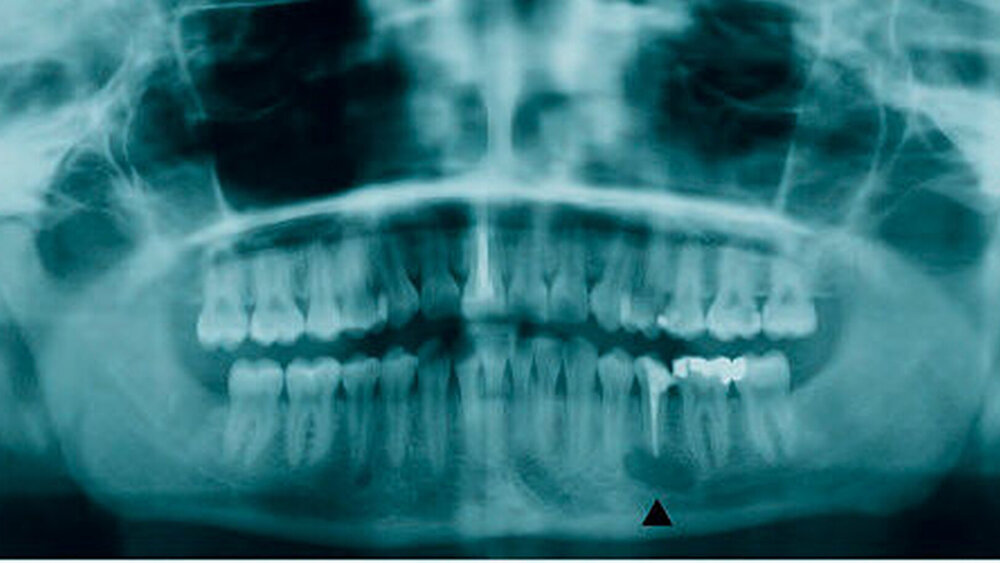

Bei der intraoralen Inspektion zeigte sich der Zahn 35 perkussionsnegativ, die Vitalitätsprobe der Zähne 35 bis 31 war ebenfalls negativ. An den Zähnen 36 und 37 fiel sie positiv aus. Die Mucosa der vestibulären Umschlagfalte von regio 35 bis 32 wies eine Anästhesie auf. Im Versorgungsgebiet des N. lingualis ließen sich keine Ausfälle dokumentieren. Bei der extraoralen Untersuchung waren die Spitz-Stumpf-Diskrimination und die Zweipunktdiskrimination der Kinnregion sowie der Unterlippe linksseitig im Sinne einer vollständigen Anästhesie erloschen. Im Versorgungsgebiet des N. mentalis der Gegenseite fand sich ein regelrechter Befund. In dem zusätzlich durchgeführten Orthopantomogramm (Abbildung 1) verstärkte sich der Verdacht, dass Sealermaterial in den Canalis mandibularis gelangt war und zu einer Schädigung des N. alveolaris inferior geführt hatte. Es wurde entschieden, eine Inspektion des Nervus alveolaris inferior links mit Entfernung des überstopften Fremdmaterials und eine Wurzelspitzenresektion am Zahn 35 in Intubationsnarkose durchzuführen.